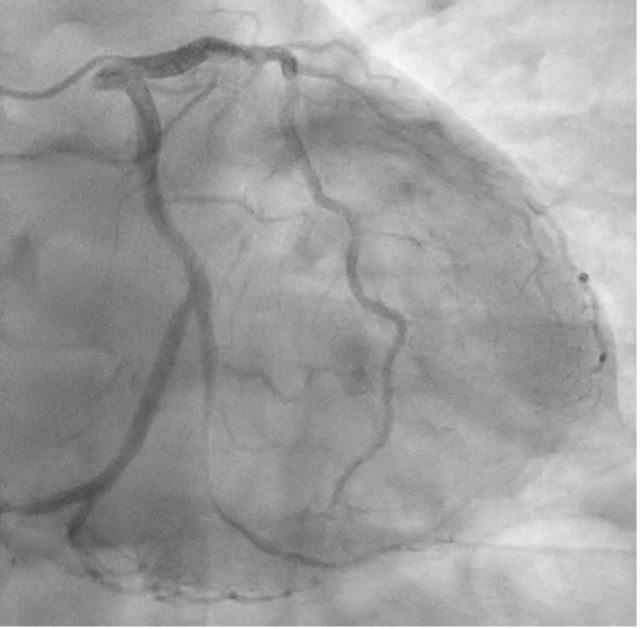

CAG shows mild diffuse stenosis at mid to distal LAD, severe diffuse stenosis at obtuse marginal, and mild diffuse stenosis at RCA (Pic 1, 2, 3).